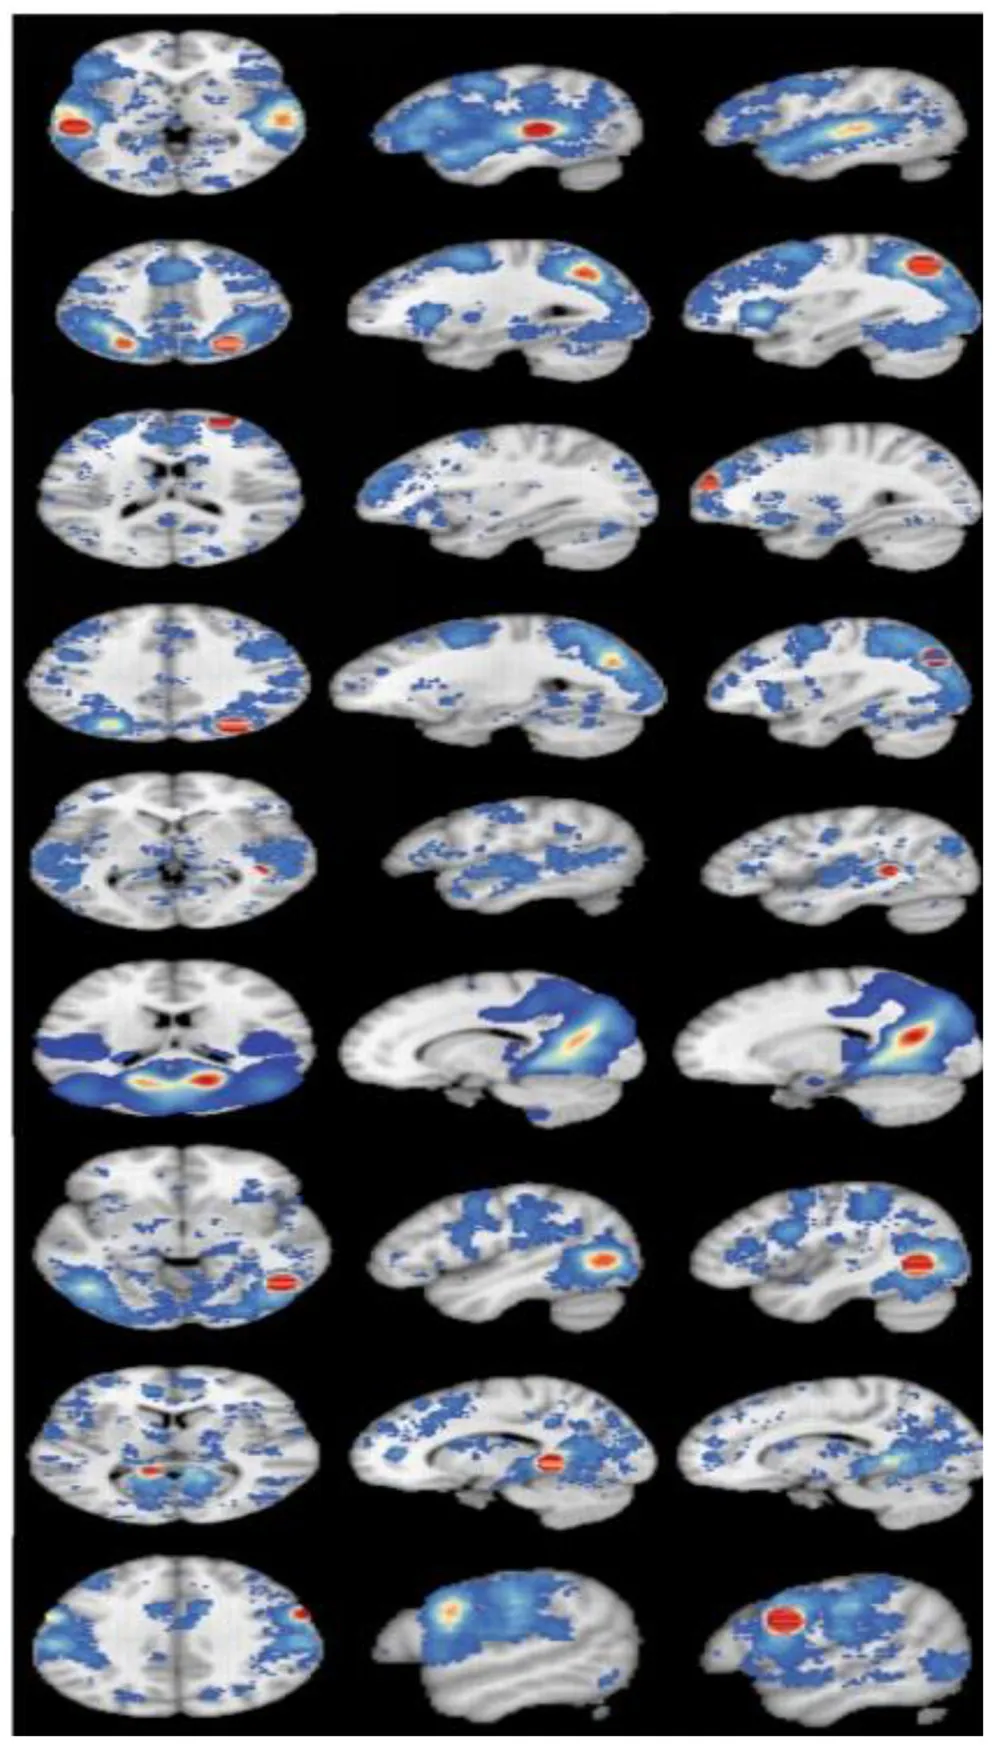

The Overall Analysis of Activity Results

Among the 14 studies that assessed brain activation during inhibitory control tasks after exercise, the exercise groups (EGs) show increased brain activation compared to the control groups (CGs) in six clusters: (1) superior temporal gyrus (BA 22), (2) precuneus (BA 7 and BA 19), (3) superior frontal gyrus (BA 10), and (4) cuneus (BA 19). Five regions showed reduced brain activation: (1) caudate gray matter, (2) posterior cingulate cortex (BA 31), (3) middle temporal gyrus (BA 37), (4) parahippocampal gyrus, and (5) precentral gyrus (BA 6), as shown in Table 4 and Figure 2.

Figure 2

Results of the ALE meta-analysis show increased and reduced activation for inhibitory control in the EGs compared with CGs. Uncorrected p < 0.001 and cluster size >100 mm3 (from A–D: activation is increased, and from E–J: activation is decreased).